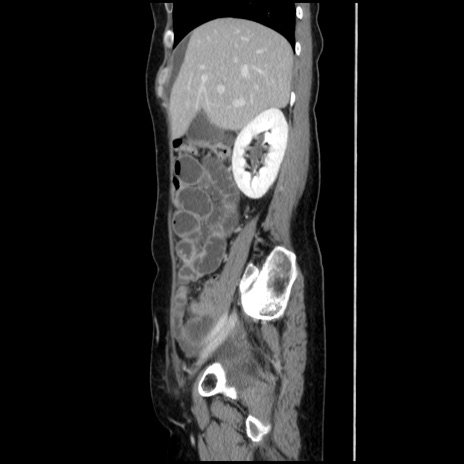

冠状断像

【症例】40歳代 女性

【主訴】上腹部痛、嘔気・嘔吐

【現病歴】約9時間前頃から急に上腹部痛、嘔気、嘔吐が出現。改善しないため救急要請。

【既往歴】子宮頚癌(広汎子宮全摘術、放射線療法)、腸閉塞

【身体所見】腹部:平坦、軟、腸雑音亢進、上腹部を中心に腹部全体に圧痛あり。

【データ】WBC 8400、CRP 0.03